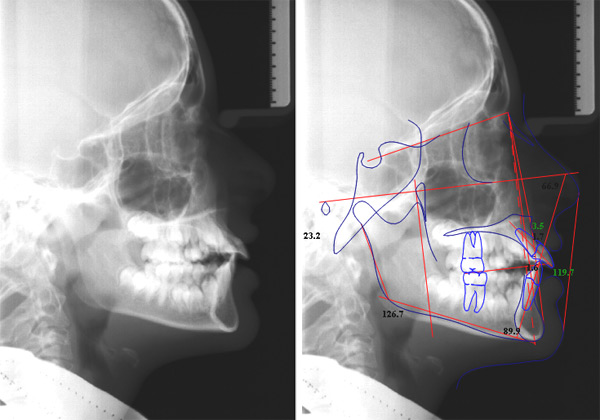

una teleradiografia laterale (che serve per eseguire le misurazioni cefalometriche utili alla formulazione di un piano di trattamento ortodontico)

Con questi esami lo specialista esegue un tracciato cefalometrico, e se necessario inizia un trattamento ortopedico funzionalizzante che utilizza un apparecchio mobile (i bambini lo possono mettere e togliere da soli) con il quale si può guidare la crescita dei denti in posizione corretta, guidare la crescita delle basi ossee e correggere abitudini viziate come succhiare il dito e respirare con la bocca aperta.